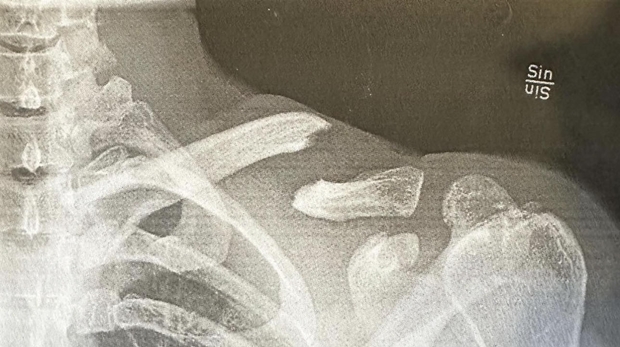

La mala fortuna nuevamente con el piloto español Josep García (KTM Factory), que en la segunda fecha del EnduroGP en Suecia, fue al piso de mala manera en un enduro test, sufriendo fractura múltiple de clavícula izquierda, junto al codo dislocado. El nacido en Súria, venía liderando la carrera justo cuando parecía haber encontrado su ritmo, ganando el día anterior y metiendo presión a los pilotos de Beta, Brad Freeman y Steve Holcombe, ahora el “joven maravilla” será intervenido quirúrgicamente en España, teniendo que esperar una recuperación récord de tres semanas, si quiere estar presente en Eslovaquía, más allá de haber cedido valioso terreno por el campeonato, al abandonar en Skövde.

La imagen muestra la fractura múltiple en la clavícula del ex campeón del mundo que deberá regresar desde cero